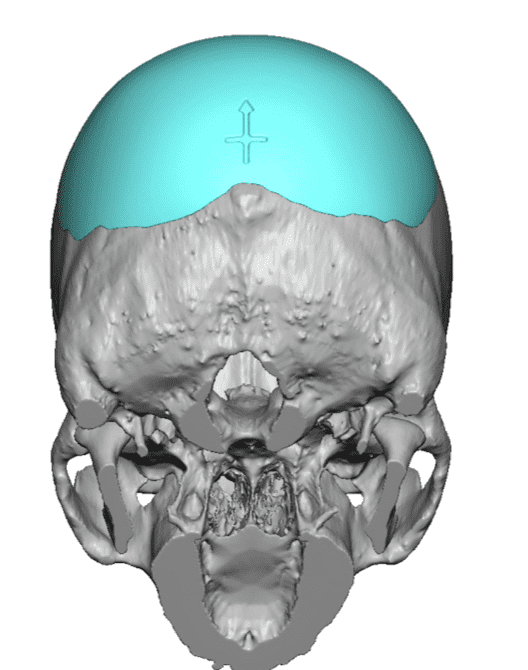

Desire for an improved head shape so that it looks rounder and not so peaked or sloped.

Placement of custom skull implant for parasagittal augmentation to create a rounder head shape. An example of what appears to be a high sagittal crest that is really low parasagittal skull areas.

Desire for an improved head shape so that it looks rounder and not so peaked or sloped.

Placement of custom skull implant for parasagittal augmentation to create a rounder head shape. An example of what appears to be a high sagittal crest that is really low parasagittal skull areas.